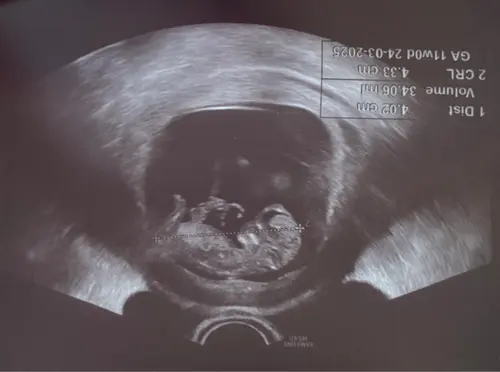

Ahja ik heb wel een 13weken echo staan met 13+5 dus miss kunn3n ze t dan al ...

Ik was precies 14 weken met de 13 weken echo, ze mogen het inderdaad niet zeggen, ook niet als ze het al kunnen zien... De echoscopiste versprak zich wel twee keer en ik dacht zelf ook het geslacht te zien, maar goed, dan kan ook een gewone verspreking zijn en ik ben ook geen pro in het geslacht herkennen natuurlijk. Dus een pretecho is altijd aan te raden als je het wilt weten. En natuurlijk super leuk om extra naar die kleine te kunnen kijken 🥰